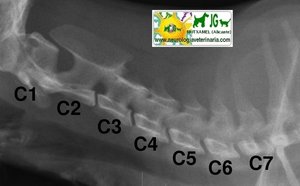

Radiografía columna cervical felina. Proyección ventrodorsal |

Radiografía columna cervical felina. Proyección latero-lateral |